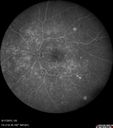

Syphilitic Chorioretinitis503 viewsSevere outer retinal atrophy and RPE non-geographic atrophy from syphilis. Vision improved from 20/63 to 20/32 with therapy. Images look a lot like DUSN. Patient had several surgeries (vitrectomy for floaters, vitrectomy for macular pucker, Avastin injections and macular laser for edema) prior by other retina specialists prior to being correctly diagnosed and treated.Feb 06, 2017